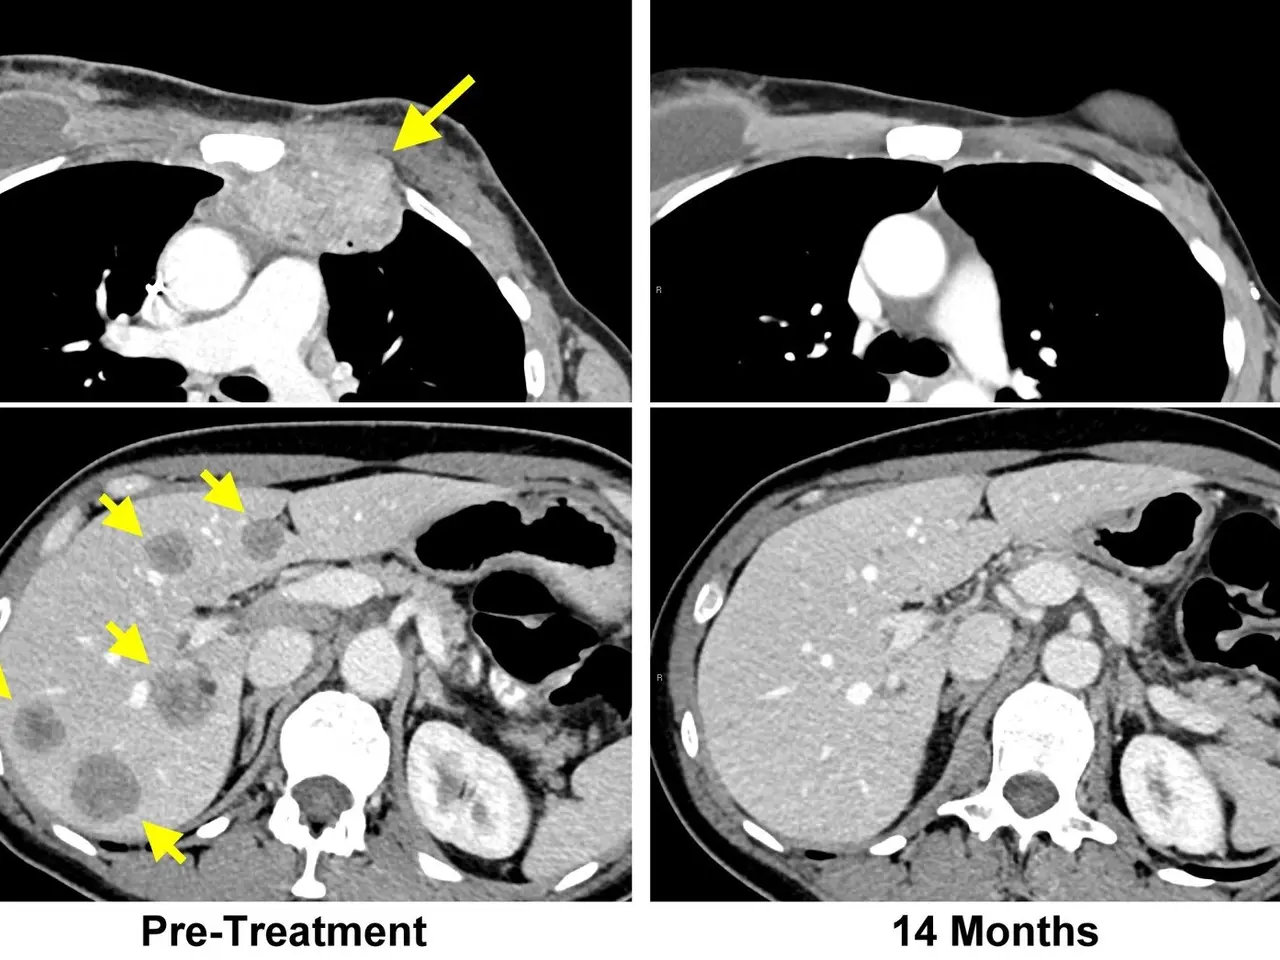

The image shows a ct scan of a patient's chest with a yellow arrow pointing to the left and a black...

The image shows a ct scan of a patient's chest with a yellow arrow pointing to the left and a black and white image of the brain with the words "pre-treatment" and "14 months" written at the bottom.